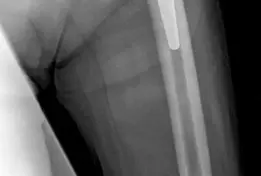

![وصف طبي دقيق للمريض](https://www.hutaifortho.

صورة طبية: جراحة مراجعة مفصل الورك: حلول لتحديات إعادة بناء الحق الحقي بعد استبدال المفصل على مرحلتين